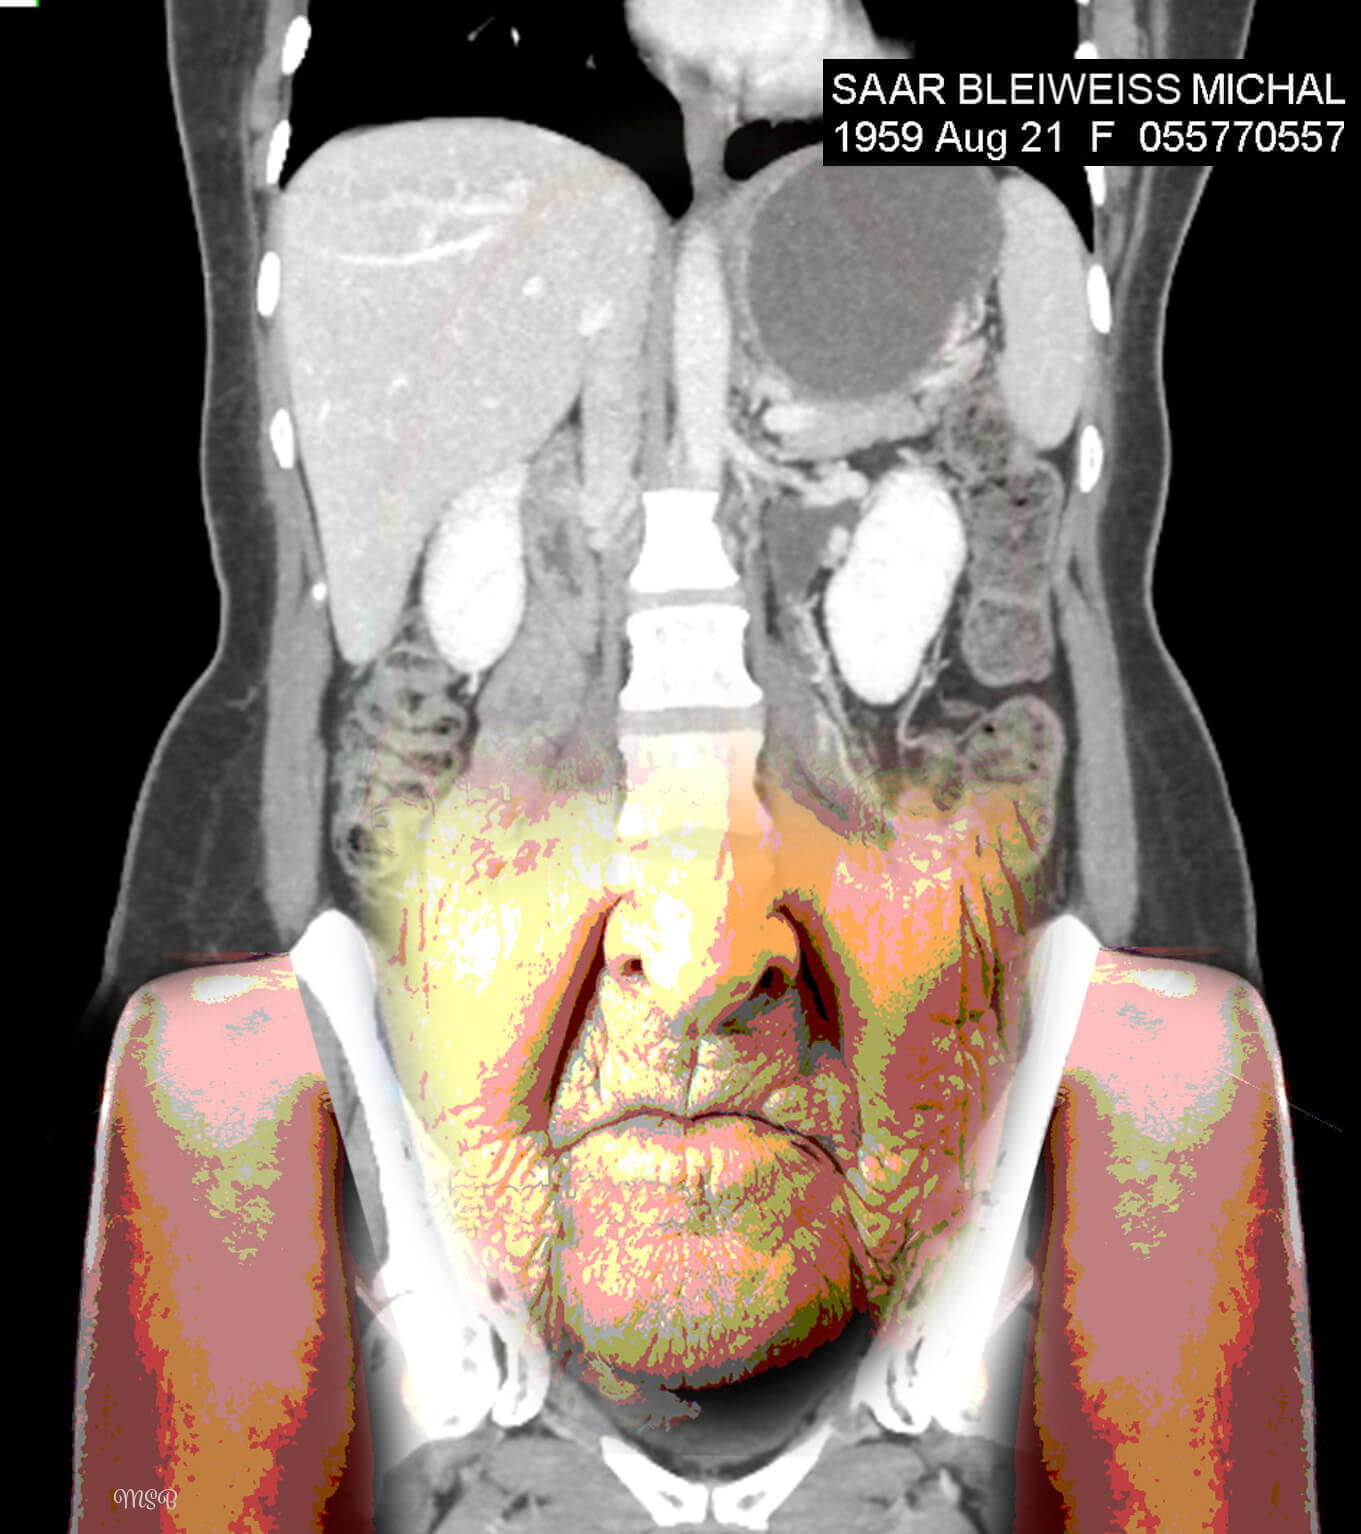

A reimagining of “self,” by Michal Saar-Bleiweiss

A few years ago, I became ill with Nephrostomy and had to undergo surgery. I was sitting with my husband, Mark, at a clinic in Ramat Aviv, Israel, in the office of a professor who specializes in CT* decoding. There, on two huge screens, for the first time I saw my body from the inside, and it was at this moment that my creative impulse arose.

The images before me were entirely in black and white, devoid of personality or character. There was no sign of the Michal that was me, and I felt a great desire and need to take these images to reinstate Michal, the person. When we returned home, I was curious about how I would feel when I looked at the images again—but this time on my computer screen. What I saw created an emotional storm within me.

This storm opened my “third eye,” enabling me to look inside myself. In my imagination I saw colors, dimensions, and expressive features, such as eyes. This was probably my way of internalizing my new reality, digesting what is going on inside me and brushing off my fears and pain. I wanted and needed to wake up each morning with a new smile and the ability to cope.

Having released the pain from the CT images, I found myself opening the next chapter in my imagination—creating digital collages.